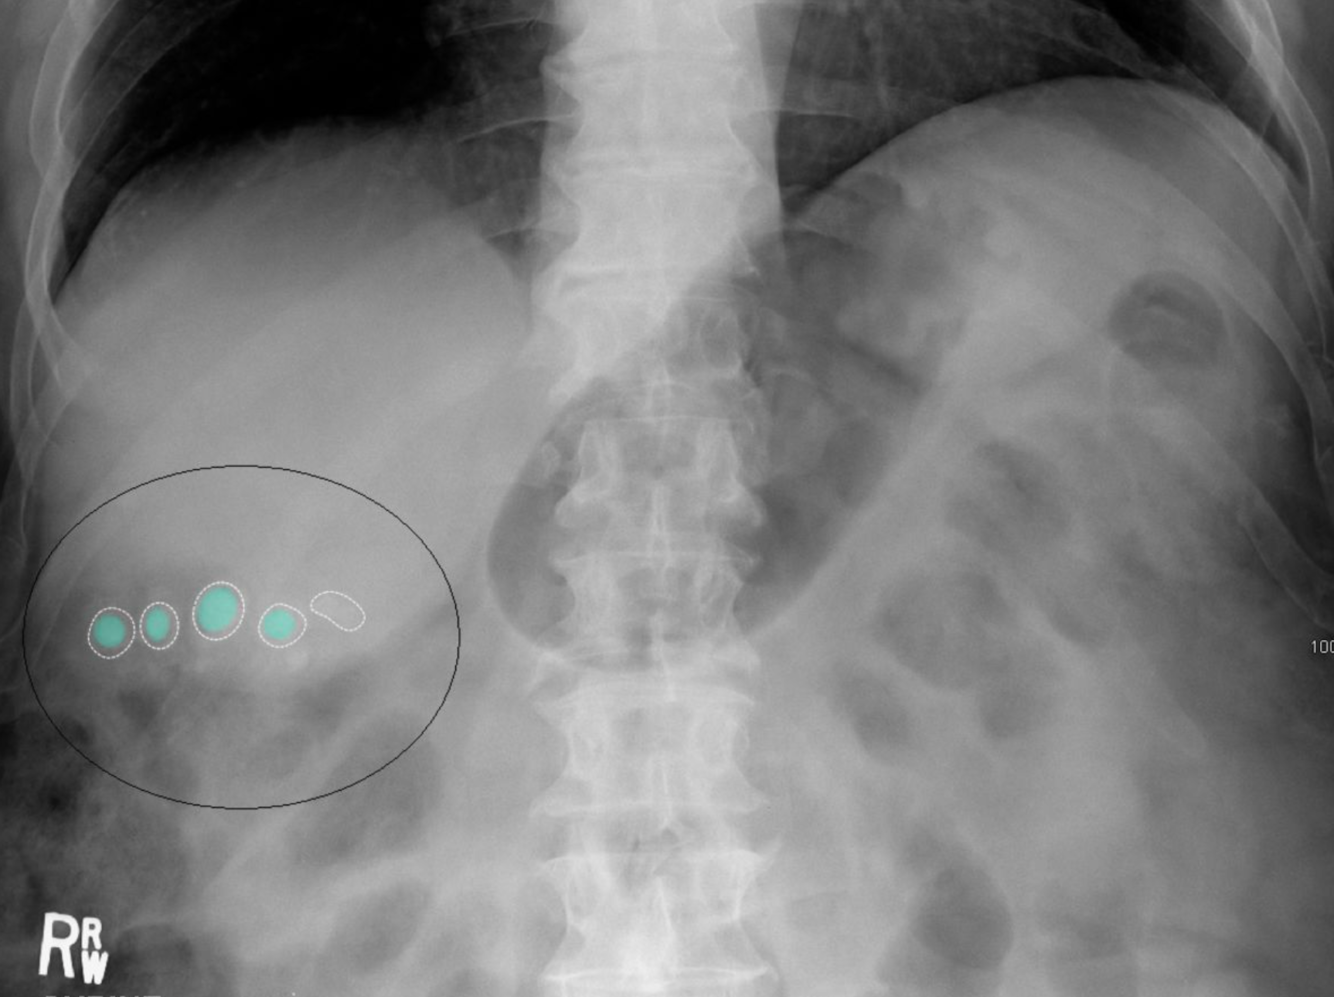

Calculs de la vésicule biliaire

Radiographie de l’abdomen (vue AP ; décubitus dorsal)

Plusieurs structures calcifiées arrondies sont visibles dans le quadrant supérieur droit (cercle noir). Beaucoup ont un aspect feuilleté, avec une calcification centrale dense (verte) entourée d’un anneau intérieur clair et d’un anneau extérieur calcifié (contour blanc).

Les calculs de cholestérol pur, le type le plus courant de calculs biliaires, sont radiotransparents sur les radiographies abdominales. Le pigment noir et les calculs biliaires mixtes peuvent contenir suffisamment de calcium pour être radio-opaques.